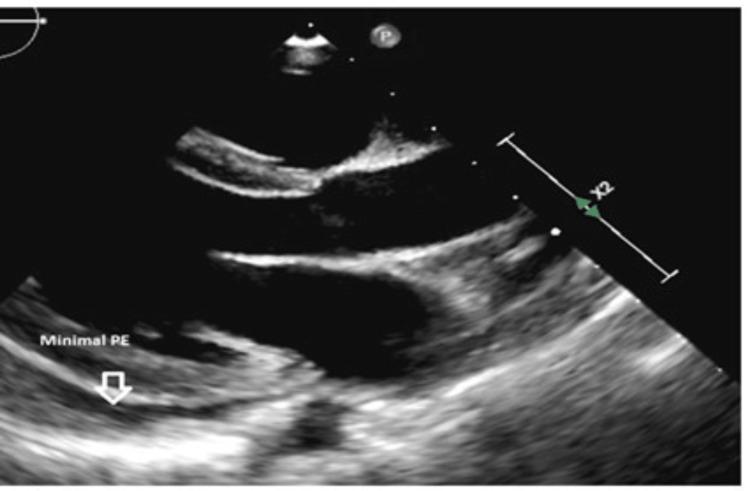

Pericardial effusion is an abnormal accumulation of fluid in the pericardial cavity. It can be associated with various cardiac and non-cardiac disorders. Dense deposit disease (DDD) is a rare kidney disease caused by uncontrolled activation of the alternative complement pathway. We are reporting a seven-year-old male child who was diagnosed to have DDD approved by renal biopsy and presented with shortness of breath, cough, and fever. Chest X-ray displayed cardiomegaly. Thereafter, echocardiography showed massive pericardial effusion and left ventricle compression with a risk for cardiac tamponade. He subsequently underwent pericardiocentesis with the removal of 450 ml of pericardial fluid. The patient's edema was not correlated with the described amount of drained pericardial fluid. To the best of our knowledge, this is the first reported case of significant pericardial effusion carrying the risk of cardiac tamponade associated with DDD. With this report, we would like to highlight the importance of cardiac assessment in patients with DDD, in particular those with nephrotic range proteinuria who present with cardiac symptoms and cardiomegaly.

心包积液是指心包腔内异常积聚液体。它可能与各种心脏和非心脏疾病相关。致密沉积物病(DDD)是一种由替代补体途径不受控制地激活引起的罕见肾脏疾病。我们报告一名七岁男童,经肾活检确诊为DDD,出现呼吸急促、咳嗽和发热症状。胸部X线显示心脏扩大。此后,超声心动图显示大量心包积液和左心室受压,有心脏压塞风险。他随后接受了心包穿刺术,抽出450毫升心包积液。患者的水肿与所描述的抽出心包积液量无关。据我们所知,这是首例报道的与DDD相关的有心脏压塞风险的大量心包积液病例。通过本报告,我们想强调对DDD患者进行心脏评估的重要性,特别是那些出现心脏症状和心脏扩大的肾病范围蛋白尿患者。